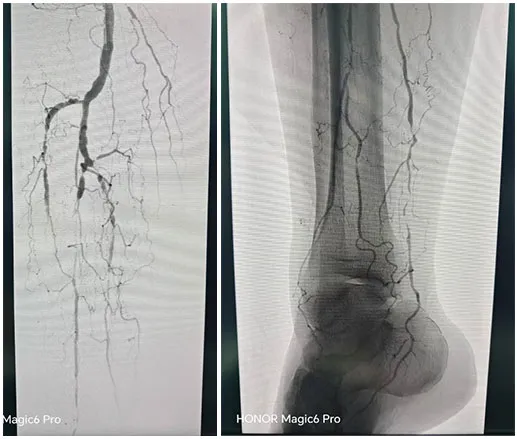

手术˜q‡ç¨‹åQšæœ¯ä¸­é€ åª„½Cø™‚¡‹¹?è…?è†ä¸‹èŠ‚æ®µæ€§ç‹­½H„闭塞,多å‘é’™åŒ–ã€‚ä¿æŠ¤ä¼žä¸‹å‡å®¹ï¼Œä½†è¡€½Ž¡é’™åŒ–局部难以推˜q›ï¼Œå‡å®¹¾l“æŸåŽï¼Œäºˆä»¥¾U¦æŸåž‹è¯ç‰©çƒå›?*150mmã€?*200mm全程处ç†åQŒéž˜å†…造媄昄¡¤ºç‹­çª„ŒDµå®Œå…¨å¤é€šï¼Œå†…膜光整åQŒè¡€‹¹é€šç•…åQŒæœªè§é€ åª„å‰‚å¤–æ¸—ï¼Œæœªè§æ˜Žæ˜¾æ “å¡žã€‚æ‰‹æœ¯é¡ºåˆ©ï¼Œæœ¯åŽæ‚£è€…安˜q”ç—…æˆÑ€?/p>

手术˜q‡ç¨‹åQ?/strong>å¯ég¸å¯¼ç®¡é…åˆå»ºç«‹é€šèµ\åŽï¼Œä½¿ç”¨2.5*150mmã€?*120mmçƒå›Šæ‰©å¼ èƒ«åŽåŠ¨è„‰ç‹­çª„ŒDµï¼Œä½¿ç”¨2*80mmã€?.5*150mmçƒå›Šæ‰©å¼ è…“动脉狭½H„段åQŒé¢„扩åŽä½¿ç”¨¾U¦æŸåž‹è¯ç‰©çƒå›?*120mmã€?*150mm分别扩张胫åŽåŠ¨è„‰ã€è…“åŠ¨è„‰ã€‚å¤æŸ¥é€ åª„½Cºå†…膜光滑,无造媄剂外渗,è†ä¸‹˜qœç«¯åŠ¨è„‰ä¸¤æ”¯æ˜‘Öª„è‰¯å¥½ã€‚æ‰‹æœ¯é¡ºåˆ©ï¼Œæœ¯åŽæ‚£è€…安˜q”ç—…æˆÑ€?/p>

手术˜q‡ç¨‹åQ?/strong>å¯ég¸å¯¼ç®¡é…åˆå»ºç«‹é€šèµ\åŽï¼Œä¿æŠ¤ä¼žä¸‹ä½¿ç”¨4*150mmçƒå›Šé¢„扩张病å˜ï¼Œåˆ†åˆ«äº¤æ¢5*200mm¾U¦æŸåž‹è¯ç‰©çƒå›Šæ‰©å¼ é—­å¡žæ®µåŠè‚¡‹¹…动脉上ŒD늋­½H„处åQ?*150mm¾U¦æŸåž‹è¯ç‰©çƒå›Šæ‰©å¼ èƒ«è…“干开å£ä¸ŠŒDµï¼Œéž˜å†…造媄昄¡¤ºè‚¡æµ…å¼€å£å¤„有残余狭½H„,余闭塞段完全å¤é€šï¼Œå†…膜光整åQŒè¡€‹¹é€šç•…åQŒå¼•å…¥DES6*40m支架一枚予以股‹¹…å¼€å£å¤„释放åQŒå¤æŸ¥é€ åª„æç¤ºç‹­çª„解除åQŒæœªè§é€ åª„剂外渗,è†ä¸‹˜qœç«¯åŠ¨è„‰å„分支显å½Þp‰¯å¥½ï¼Œæœªè§æ˜Žæ˜¾æ “å¡žã€‚æ‰‹æœ¯é¡ºåˆ©ï¼Œæœ¯åŽæ‚£è€…安˜q”ç—…æˆÑ€?/p>